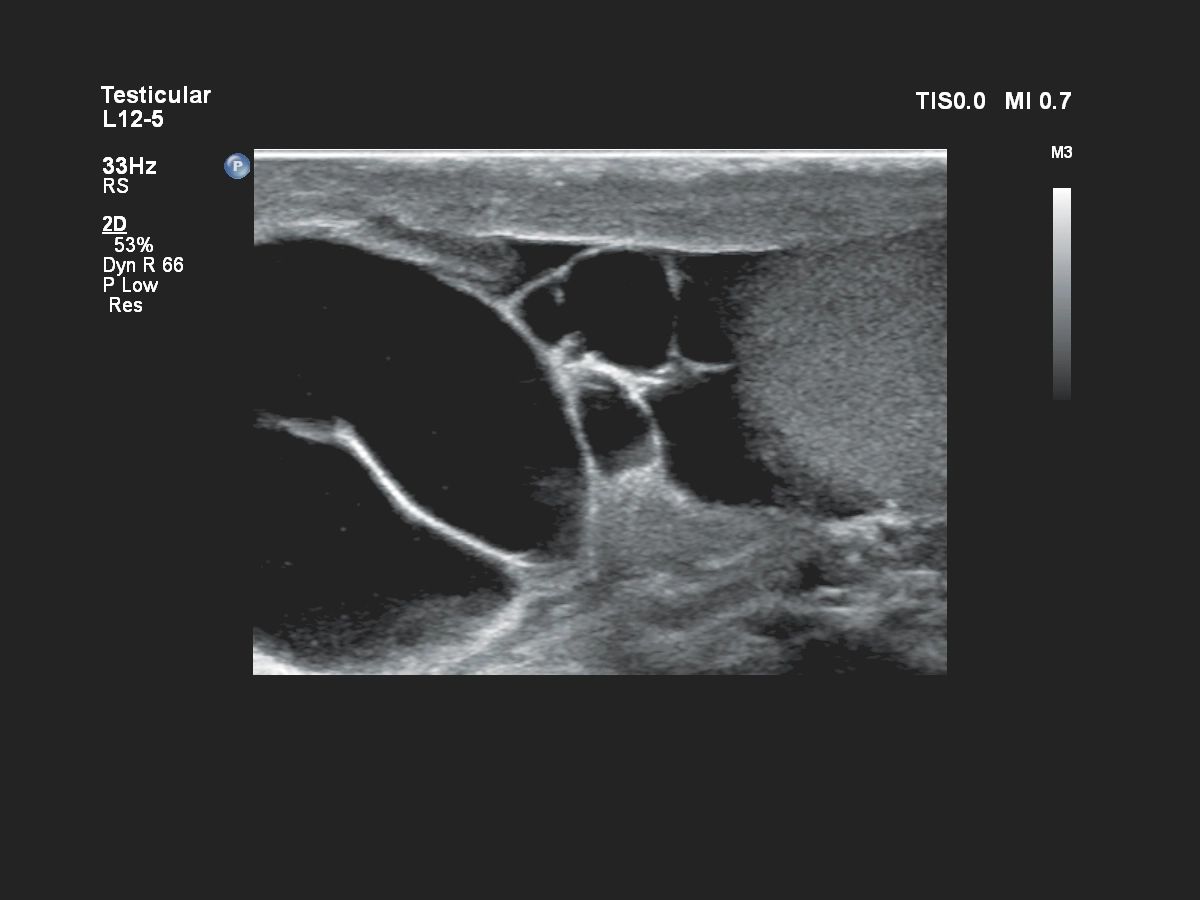

- Малые и поверхностные органы

- Урология и исследования предстательной железы

УЗИ датчики для Philips Affiniti 70

Набор совместимых датчиков полностью закрывает потребность в различных исследованиях. УЗИ аппарат Philips Affiniti 70 поставляется вместе с 4 датчиками:

- Линейный – Philips L12-3